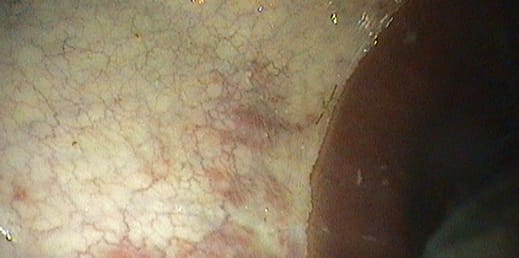

Grade 0:

Stomach lining is intact. No appearance of reddening.

Grade 1:

Stomach lining is intact. Areas of reddening, yellowing or thickening.